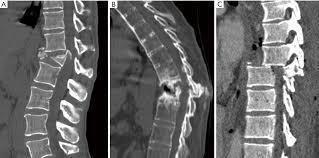

Clasificacion

Las fracturas por compresión en cuña son el resultado de una falla aislada de la columna anterior debido a la flexión hacia adelante. . En las fracturas estables por estallido, las columnas anterior y media fallan debido a una carga de compresión, sin pérdida de integridad de los elementos posteriores. En las fracturas por estallido inestables, las columnas anterior y media fallan en la compresión y la columna posterior se rompe. La columna posterior puede fallar en compresión, flexión lateral o rotación. Existe una tendencia a la cifosis postraumática y los síntomas neurales progresivos debido a la inestabilidad. Si las columnas anterior y media fallan en la compresión, la columna posterior no puede fallar en la distracción.  En las lesiones por distracción por flexión, el eje de flexión es posterior al ligamento longitudinal anterior. La columna anterior falla en compresión, mientras que las columnas media y posterior fallan en tensión. Esta lesión es inestable porque el ligamento amarillo, los ligamentos interespinosos y los ligamentos supraespinosos suelen estar alterados. Las lesiones traslacionales se caracterizan por una mala alineación del canal neural, que ha sido totalmente interrumpido. Por lo general, las tres columnas han fallado por corte. A nivel afectado, una parte del canal espinal se ha desplazado en el plano transversal